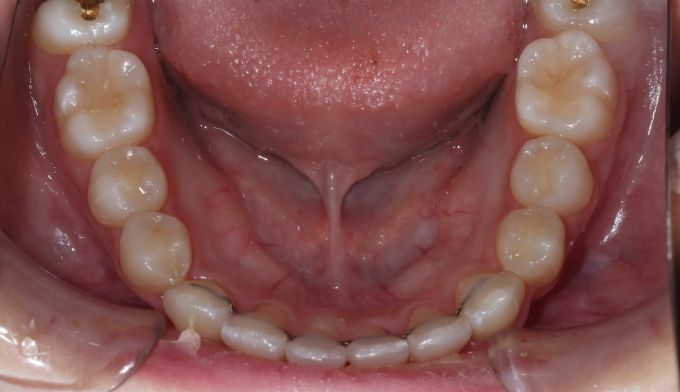

이번 케이스에서는 덧니가 심하고 공간이 매우 부족하지만, 입의 크기가 작고 입술이 얇은 편이었기 때문에 발치 없이 교정하기로 계획하였습니다.

입천장 확장과 치아배열을 통하여 총 18개월동안 치료하였습니다.